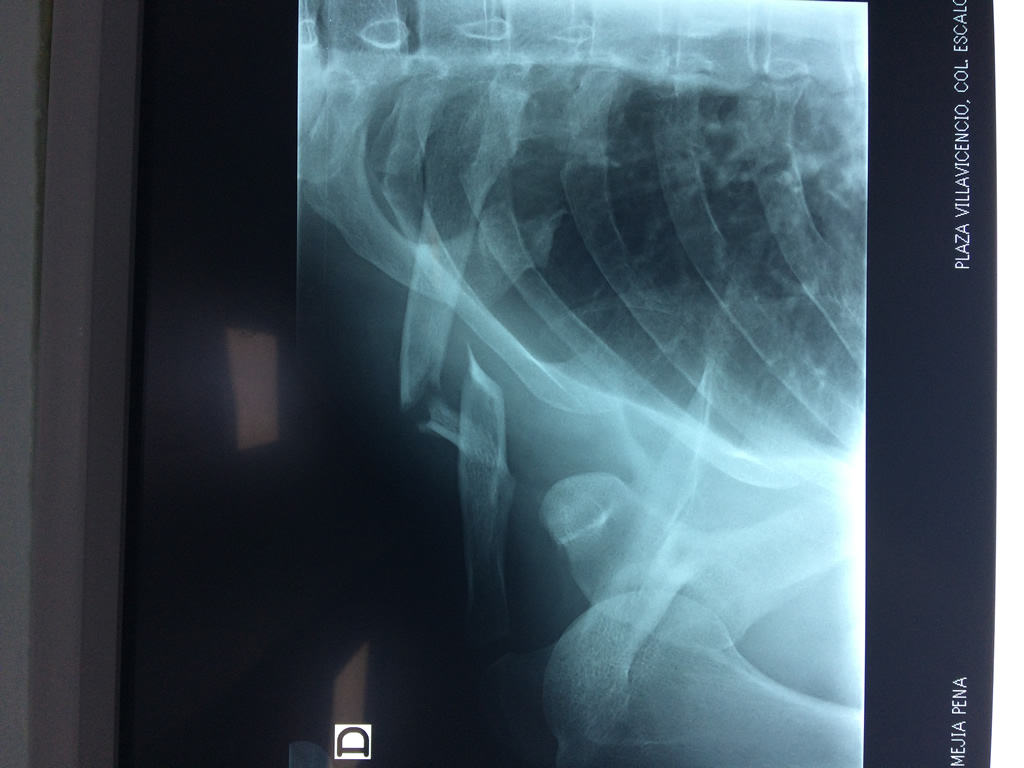

Cirugías de Húmero - Clavícula